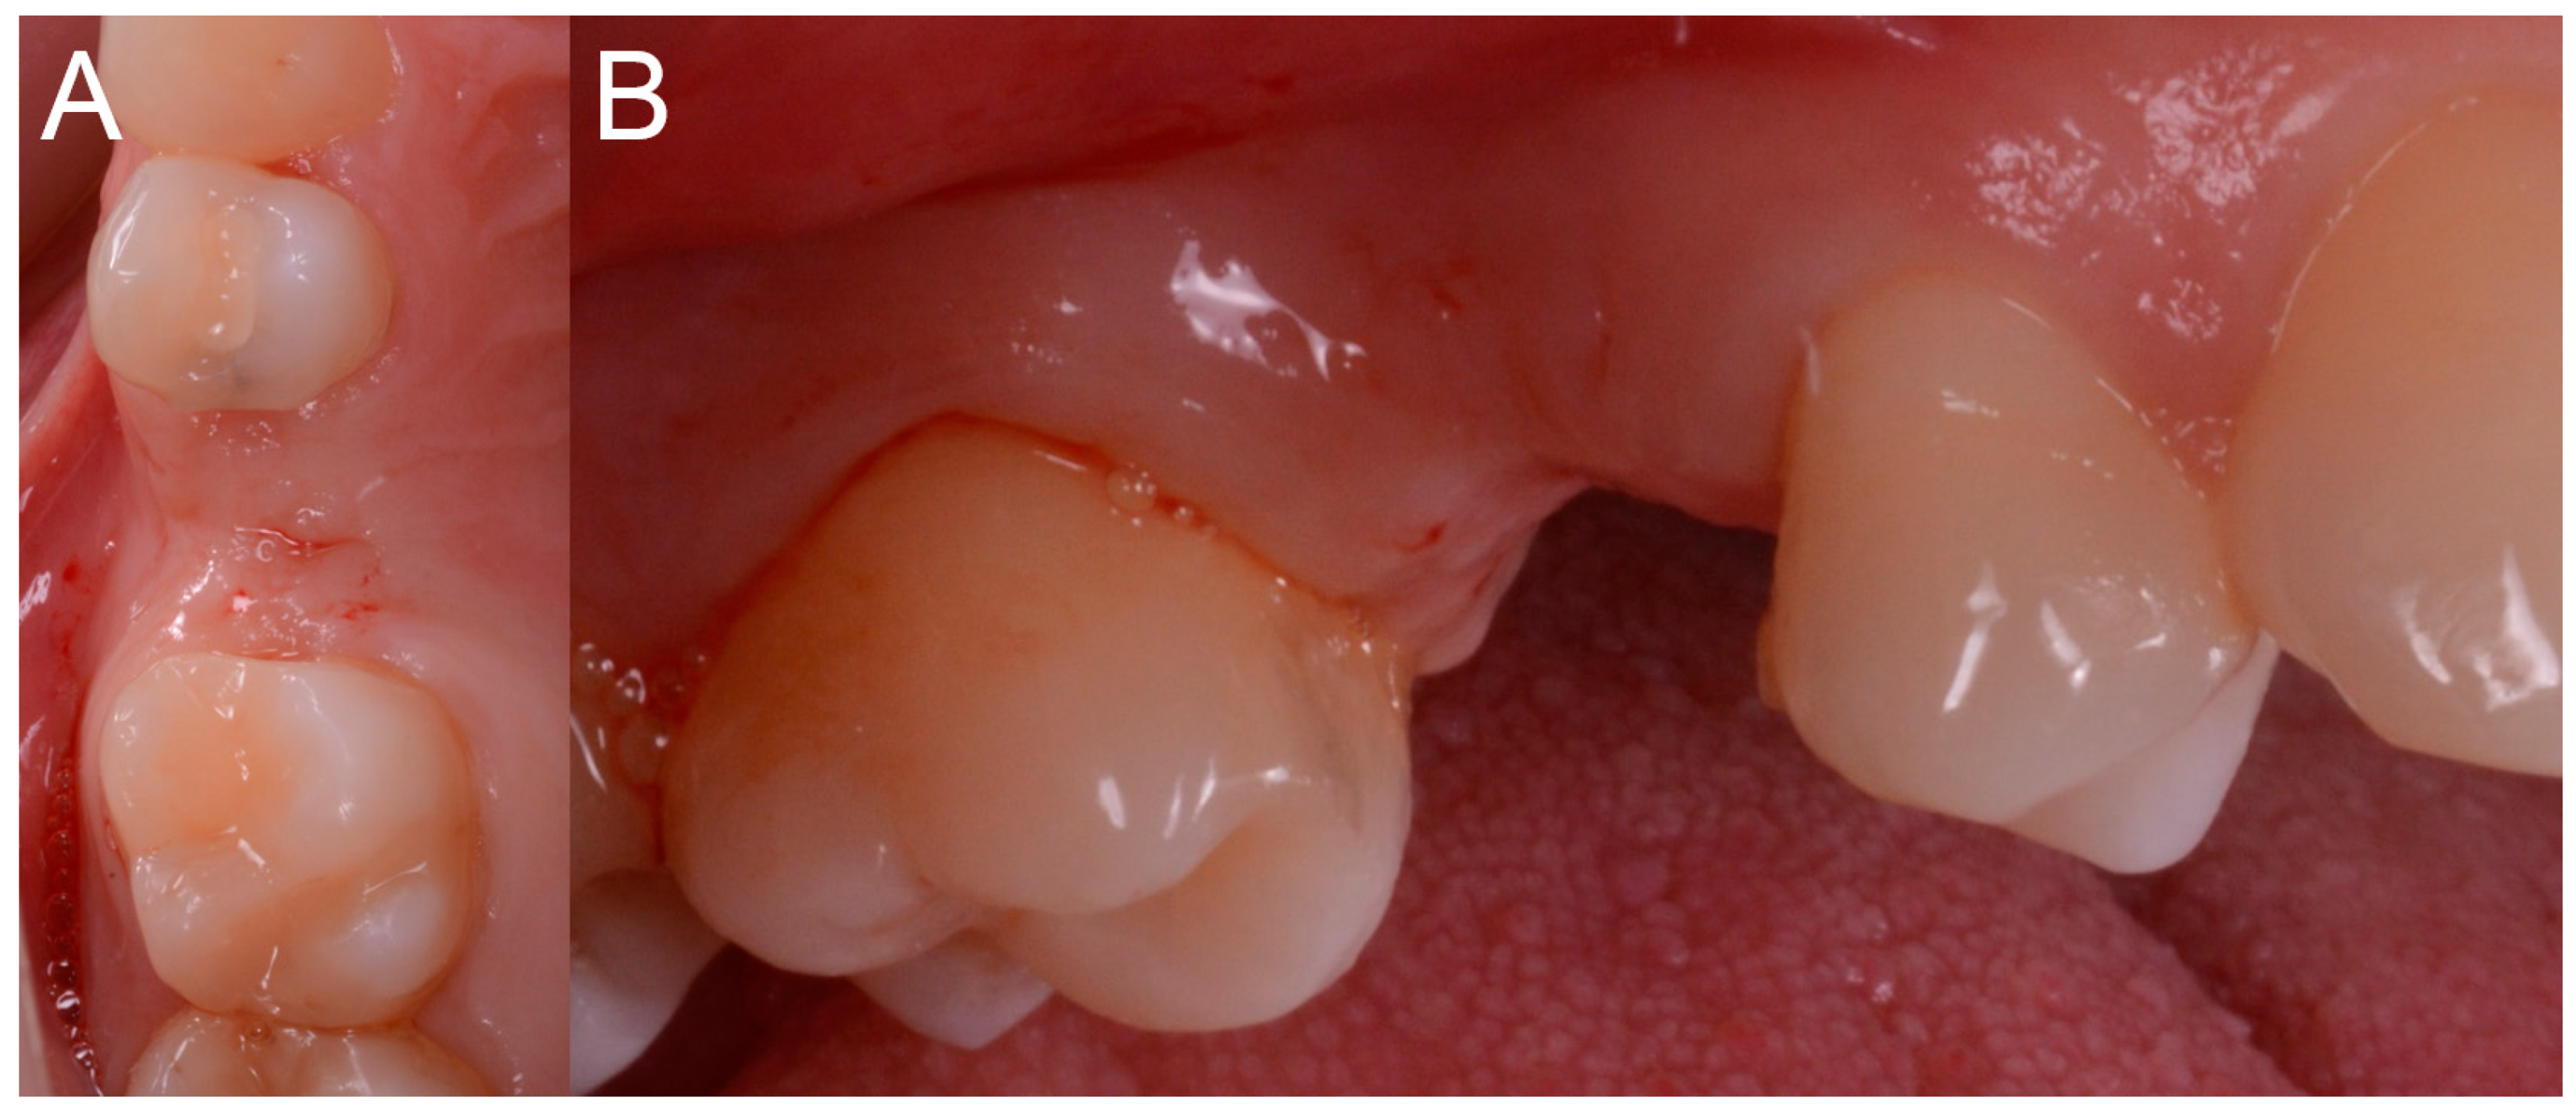

After local anesthesia by infiltration with articaine with adrenaline (at a ratio of 1:100,000) the surgeon positioned the dental-supported surgical guide, verifying its stability and the exact adaptation on the occlusal surfaces of the teeth (Figure 7).

Figure 7.

The surgical guide in position with the sleeve inserted in. (A) Occlusal view. (B) Lateral view.

This verification was possible thanks to the design of the surgical guide, which was open and thus allowed the surgeon to check directly the perfect fit of the template on the occlusal surfaces of the teeth. Once the adaptation of the template was verified, according to the surgical plan, the surgeon made the mucotomy, with a dedicated mucotome, through the surgical guide, in order to remove the necessary amount of gingiva and to create an access for the preparation of the implant site. Once the mucotomy ended, the surgeon began to prepare the implant site (Figure 8), in accordance with the surgical plan (and therefore with the pre-established drilling depth) and consistent with the chosen implant diameter and length.